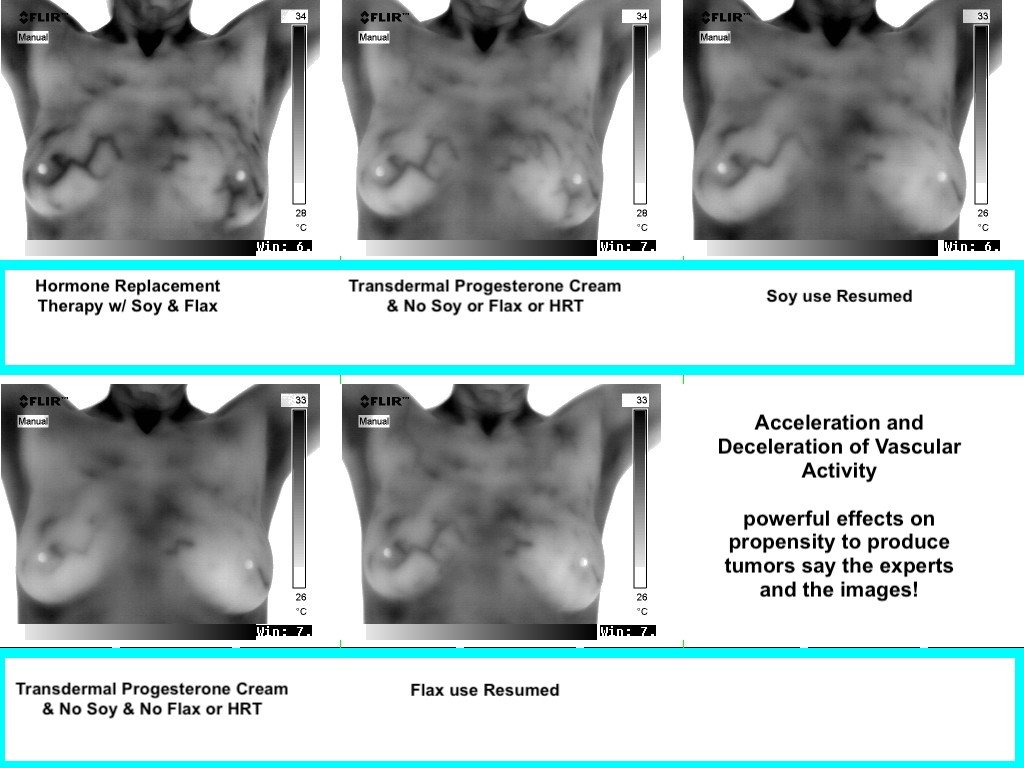

Excessive Breast Vascularity Retreats When Soy/Flax are Withheld From Diet:

BELOW: Image on Left of Soy milk Consumer & on Right is After Soy milk Consumption Ceases

Top Row of Images is Left: Consuming SOY and Right after Discontinuation of Soy

Bottom Row: Left: Same lady starts consuming FLAX milk and Right: After Discontinuation of FLAX in her diet.

ABOVE: Same woman After Consuming Flax milk (L) and After Flax Milk Consumption Ceases (R)

BELOW: Images Showing LEAST VASCULARITY occurred while using progesterone cream and abstaining from soy, flax, HRT ( meaning estrogen supplementation -technically progesterone cream is a form of HRT too but isn’t typically thought of as such).